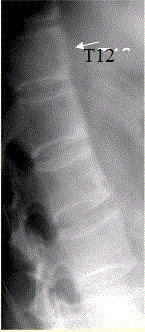

问题 患者男,35岁,外伤后行腰椎CR检查,结果如下图。 强直性脊柱炎的主要病理改变为

选项 A.附丽病 B.滑膜炎 C.关节囊、韧带附着处纤维软骨增生肥大、骨赘形成 D.大量新生骨形成和骨旁骨化 E.广泛滑膜增生伴出血、含铁血黄素沉积 F.异位骨化或钙化

答案 AB